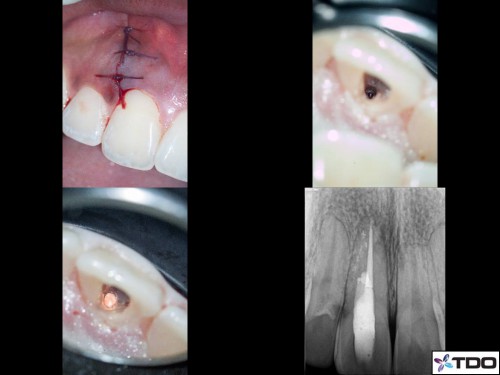

23 YF presented with pain and clinical signs of GP inside the buccal aspect of the gingiva around tooth #11 (FDI). The scan shows the buccal perforation with two GP points and an apical finding. Initially we removed all GP fragments internally and repaired the internal aspect of the perforation with SDR and interim CaOH was placed into the true canal. Second visit, the patient was asymptomatic and the surgical phase involved repairing the perforation defect with Geristore. The RCT was then completed and the access was closed with resin. Patient was very happy with the aesthetics at the follow-up and no- probing was evident at the perforation site through the buccal marginal gingiva. I hope this turns out well long-term.